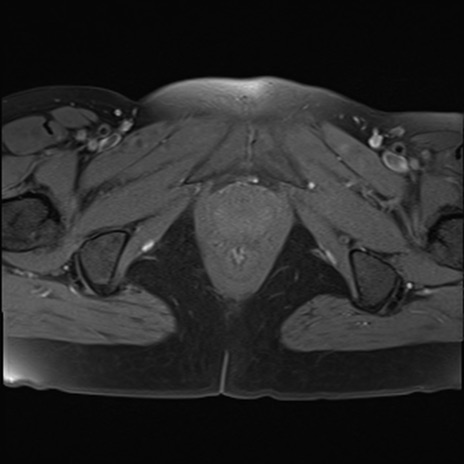

症例39 脂肪抑制T1WI(横断像)

MRI(4日後)

T1WI(横断像)